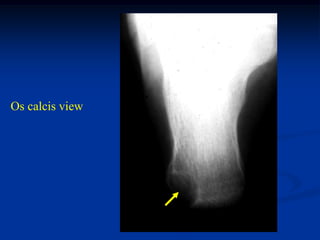

Case #566

17 year male with enchondroma os calcis

Os calcis view